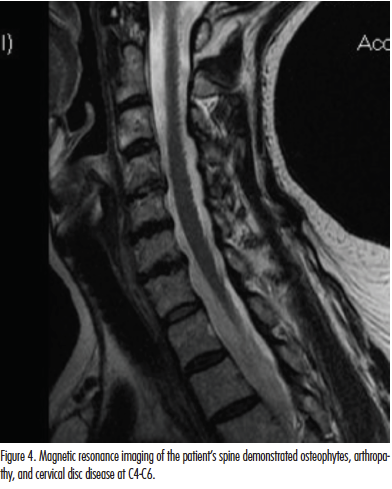

We described a concurrent case of refractory NP and BRP in a 67-year-old woman successfully controlled with cervical musculoskeletal disease management. Skin lesions in this patient cleared using our newly standardized multimodal therapy program for NP and BRP utilizing a customized clearing and maintenance phase schedule directed at cervical spinal and disc disease at C4-C6 (Figure 4). The main components of this program utilized in-office and at-home TENS and EMS, cervical acupuncture, phototherapy with narrowband UV-B for generalized pruritus control, physical therapy referral, and consultation with rheumatology and pain management. The patient was doing very well dermatologically at a 3-year follow-up with complete resolution of symptoms and remission of skin findings. She recently notified us of a new diagnosis of systemic lymphoma.